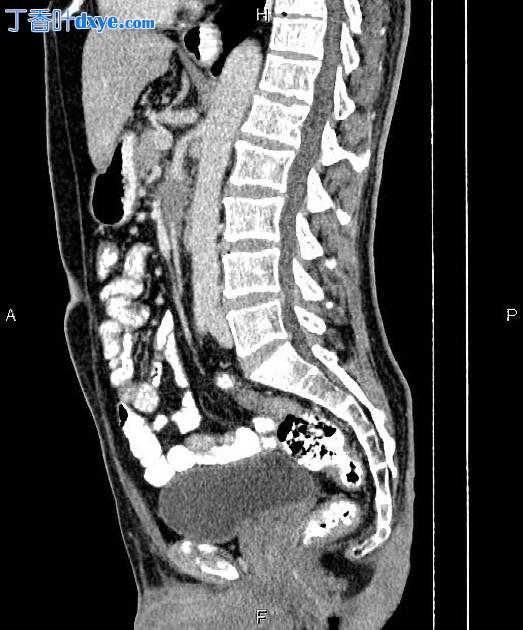

Sagittal C+ portal venous phase

胰腺钩突处观察到一个 40×25 mm 的低增强肿块,部分包裹着 SMA 和 SMV。

左肾上萼处有一块小于3毫米的小结石。

前列腺增大。

胰腺肿块; 病理证实为腺癌,有血管包裹。

影像学上,它通常在 CT 上表现为边缘较差的低密度肿块,可能包裹血管和胆总管